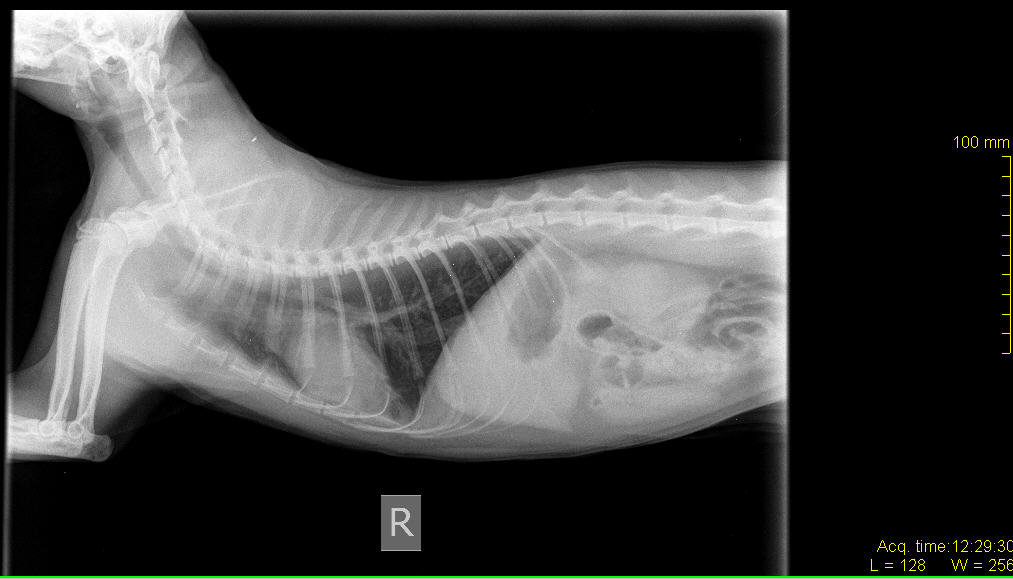

Кашель у кошек хрипы